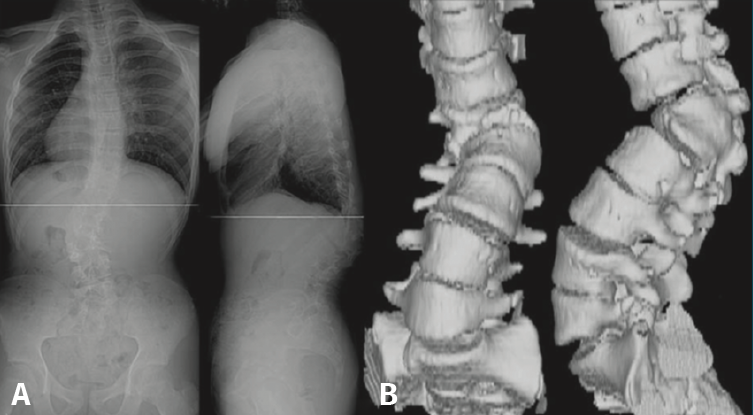

Figura 5. Espondiloartropatía degenerativa.

Otros hallazgos radiológicos frecuentes, como las anomalías congénitas de transición lumbosacra, espondilolistesis, secuelas de epifisitis, la espina bífida oculta, las escoliosis leves o moderadas, la hiperlordosis, espondiloartropatía, etc., se encuentran casi por igual en pacientes con y sin dolor lumbar (Figuras 5, 6 y 7)(22,23).

Figura 10. Escoliosis secundaria a hemivértebra.

Constituye una técnica muy útil para evaluar las anomalías anatómicas de la columna vertebral (Figura 10).

Figura 11. Malformación vertebral en resonancia y tomografía axial computarizada.

La TAC visualiza con bastante precisión el tejido óseo, siendo claramente superior a la RM para ello. También permite visualizar los tejidos blandos intra- y paraespinales, aunque la RM es muy superior en la evaluación de estos tejidos, por lo que está siendo desplazada por esta para el estudio de los problemas discales, degenerativos y radiculomedulares (Figura 11).